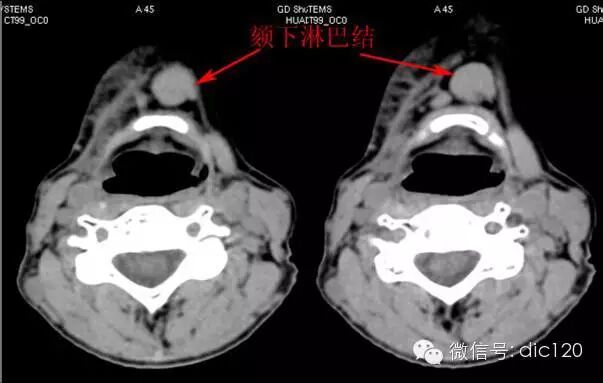

Ⅰa,包括颏下淋巴结。引流颌、下唇中部、舌尖和口底前部的淋巴结。是口底、舌前、下颌骨前牙槽突和下唇肿瘤发生隐匿性转移的高危区域。

Ⅰb区包括下颌下淋巴结,位于二腹肌前后腹、茎突舌骨肌和下颌骨体之间,接收来自颏下淋巴结、内眦、鼻腔下部、硬软腭、上下颌骨牙槽突、颊、上下唇和舌前大部的淋巴管。口腔、前鼻腔、面中部软组织和下颌下腺肿瘤易发生这一区域淋巴结转移。